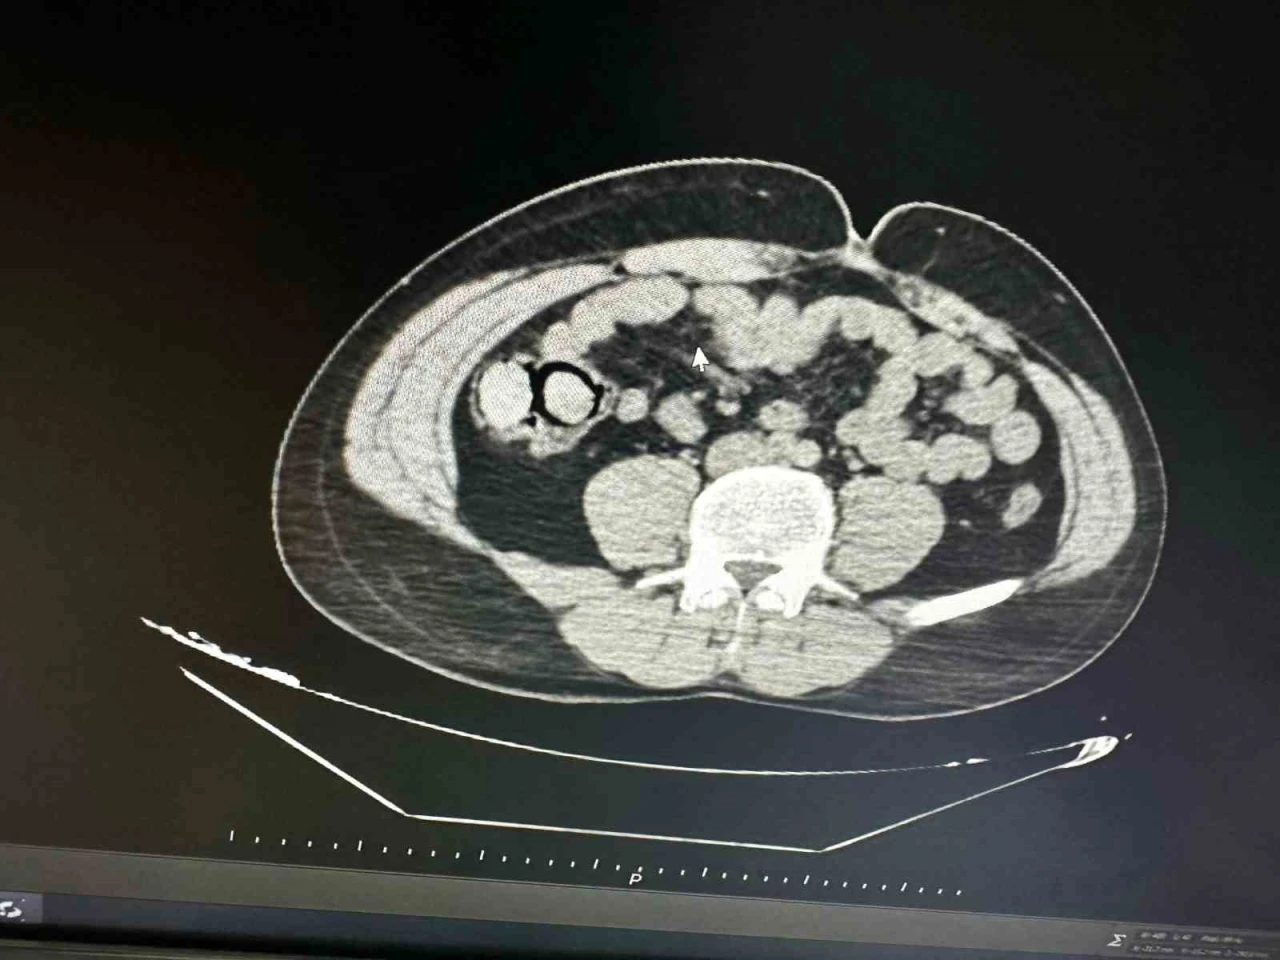

Bingöl’de akıllara durgunluk veren bir olay gerçekleşti. Otobüs yolculuğu sırasında polis ekiplerince durdurulan yabancı uyruklu iki şahsın midesinden 10 parça halinde 113 gram metamfetamin çıktı.

Bingöl Emniyet Müdürlüğü Narkotik Suçlarla Mücadele Şube Müdürlüğüne bağlı narko-timleri akıllara durgunluk veren bir uyuşturucu kaçakçılığını çözdü. Ekiplerin çalışmaları neticesinde otobüs ile Bingöl’e gelen şüpheli yabancı uyruklu 2 şahsın iç beden muayenesinde 10 parça halinde 113 gram metamfetamin maddesi tespit edildi. Emniyetteki işlemlerinin ardından mahkemeye çıkarılan 2 şahıs, uyuşturucu madde ticareti yapmak suçundan tutuklanarak Elazığ Kapalı ceza infaz kurumuna teslim edildi.